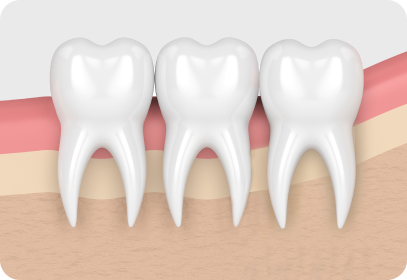

사랑니의 종류.

img-0501-3-1.jpg

수직으로 솟은 사랑니

가장 안쪽에 있는 사랑니는 칫솔이

잘 닿지 않아 관리가 어려워 충치나

잇몸 질환이 생기기 쉽습니다.

img-0501-3-2.jpg

가로로 나온 사랑니

바로 앞 어금니 뿌리를 압박해 염증을

일으키거나 턱뼈의 신경까지 손상시킬

수 있어 발치하는 것이 좋습니다.

img-0501-3-3.jpg

불완전 돌출 사랑니

비정상적인 위치에 매복되어 자란 사랑니는

염증과 통증을 일으킬 수 있으므로

발치하는 것이 좋습니다.